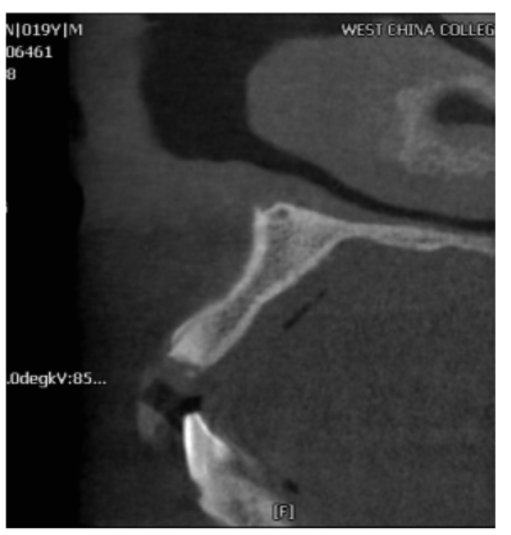

图7 术前矢状位

CBCT片显示牙槽骨密度低,正在愈合中